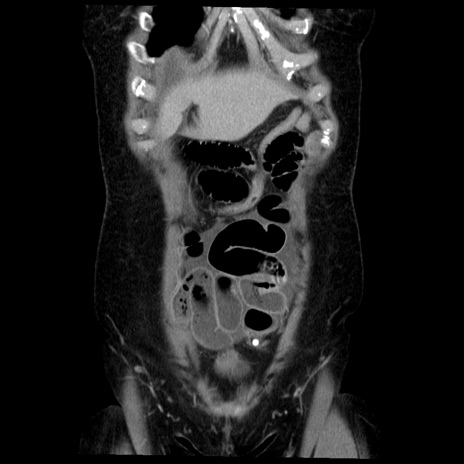

症例6(冠状断像)

【症例】50歳代女性

【主訴】下腹部痛

【現病歴】本日朝より下痢2回あり。 昼食を食べた後、嘔吐3回、下腹部痛認め、症状軽快せず、当院救急搬送。

最終食事:本日昼(生ものなし)。 昨日の夜、刺身を食ぺたとのこと。周囲に同様の症状の者なし。普段、排便は毎日あるとのこと。

【既往歴】卵巣癌術後(8年前に当院で卵巣摘出)

【身体所見】 意識清明、腹部:平坦、腸蠕動音→、やや硬、下腹部自発痛・圧痛あり、反跳痛あり、筋性防御なし。

【データ】WBC 16000、CRP 0.01